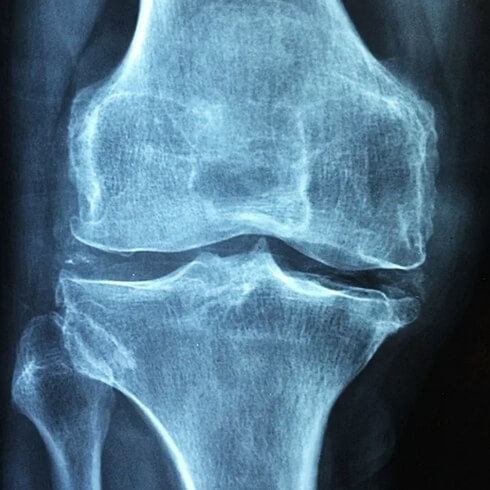

이 중에서 특히 퇴행성 관절염의 경우 노화에 따라 관절 연골이 점차 마모되어 발생하며 우리나라 어르신들의 퇴행성 관절염의 발병률이 매년 급격하게 증가하고 있습니다. 실제 50대 이상 10명 중 3명 이상은 관절염으로 고생을 하고 계신다는 통계가 있습니다.

우리 몸에서 무릎, 어깨, 손가락, 손목, 고관절 등과 같이 뼈와 뼈가 만나는 관절은 평생 동안 굉장히 많은 움직임이 있기 때문에 뼈와 뼈의 충돌을 막는 연골이라는 성분이 존재합니다.

그런데 노화에 따라 연골이 달거나 운동선수처럼 단기간에 관절을 반복적으로 사용하는 경우에는 뼈와 뼈가 직접적으로 서로 충돌하게 되어 관절의 염증이 발생하게 되고 결국 만성적인 통증으로 이어지게 됩니다. 이것이 바로 우리가 흔히 말하는 '퇴행성 관절염'이라고 부르는 질환입니다.